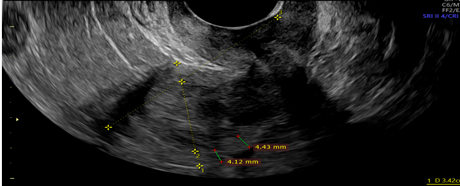

Picture1.Interrupted endometrial myometrial junction- green cursors.

Picture 2. 3D ultrasonographic view of interrupted endometrial myometrial junction, green cursor.